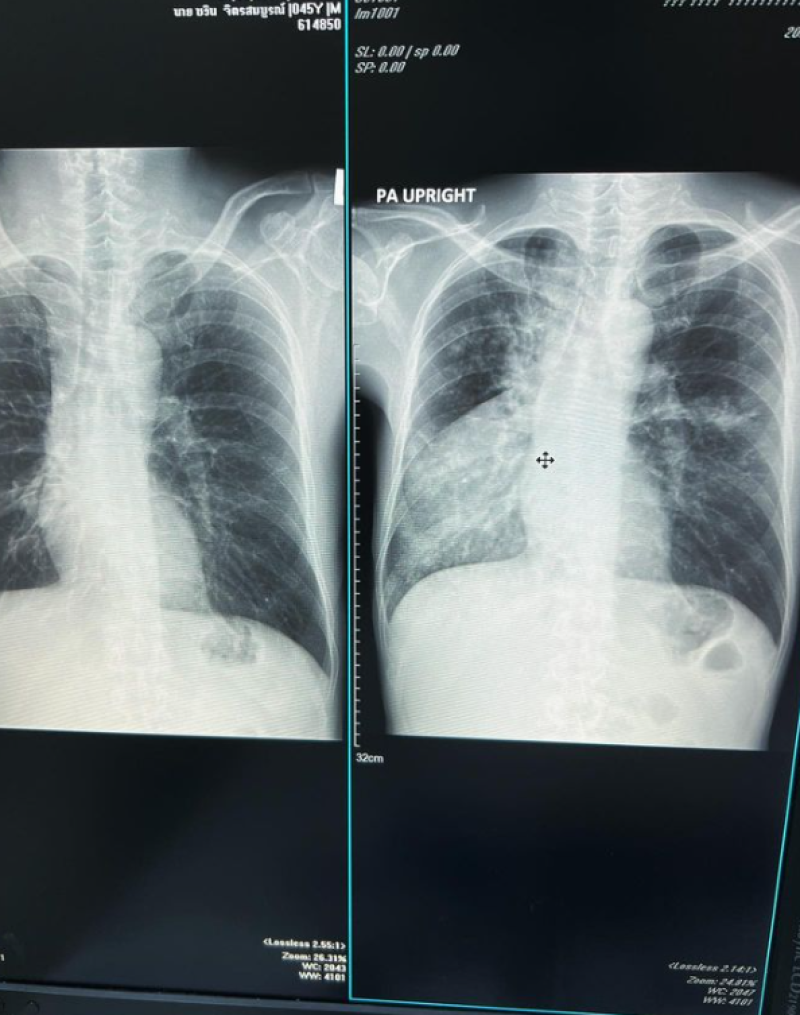

จากรณีที่ก่อนหน้านั้น นักร้องดัง อย่าง จั๊ก ชวิน ได้ออกมาเผยว่าป่วยวัณโรคต้องหยุดงานและพักรักษาตัวยาวๆ ล่าสุด ทางจั๊กได้ออกมา ข่าวดีพร้อมโพสต์ภาพ เเผ่นเอ็กซเรย์ปอด พร้อมเขียนข้อความว่า สบายใจละ หายขาด คุณหมอบอกเจอกันอีกทีปีหน้าเลย ขอบคุณมากครับ #จั๊กชวิน #juggchawin #ระนะจั๊ก_รักนะจ๊ะ # #โรงพยาบาลวิภาวดี

ภาพจาก jugg_chawin